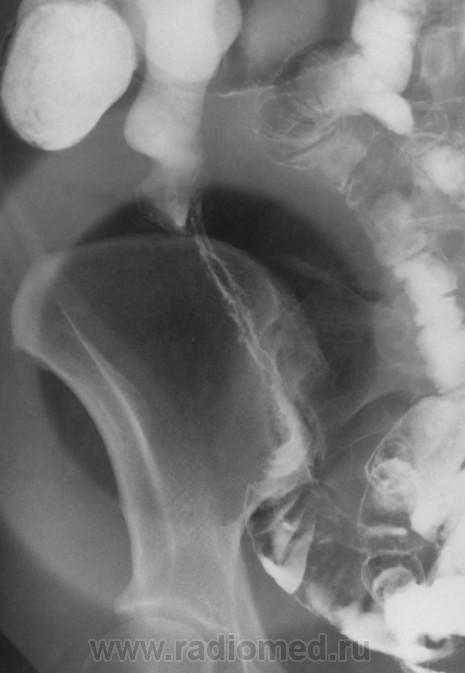

Крона vs. туб. vs. лимфома подвздошной. Цекум мобиле. Пдпеченочный аппендикс. Дивертикул сигмы.

Терминальный илеит(Крон). Респект за качество исследования, и снимков.!!!